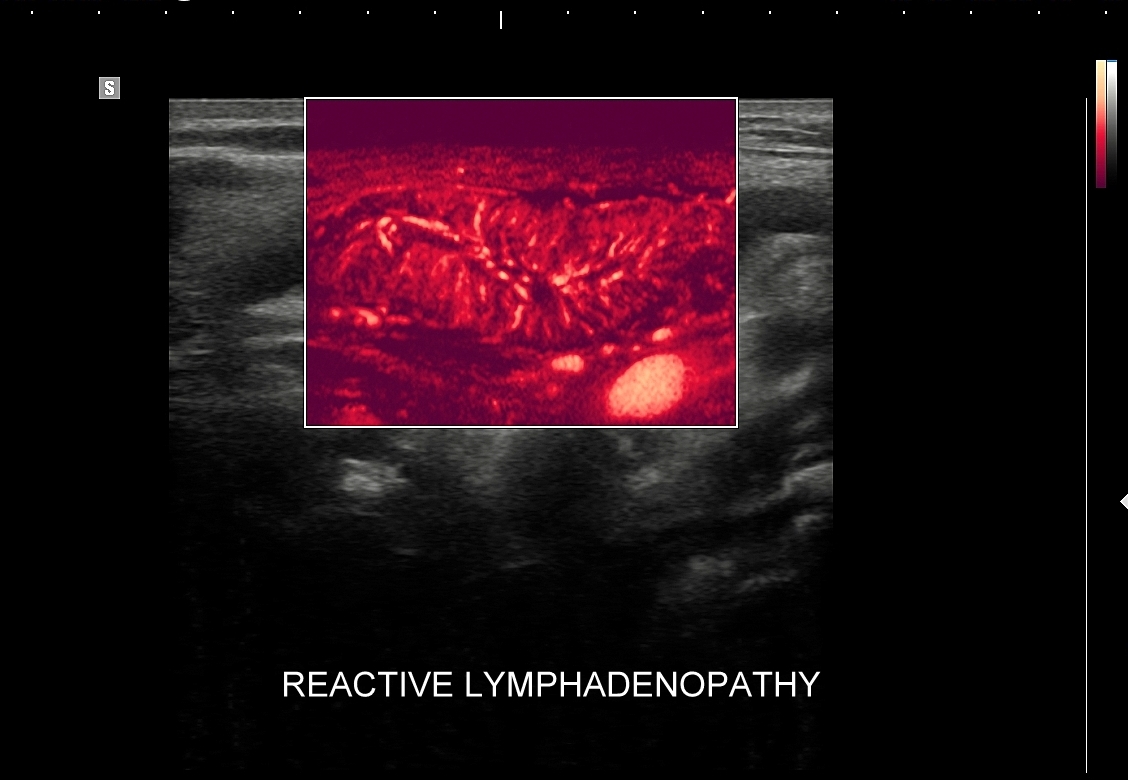

8. Patologie węzłów chłonnych.

9. Kompleksowe podejście do diagnostyki węzłów chłonnych z uwzględnieniem USG.

Multiparametryczne badanie USG (MPUS) jest rozwinięciem klasycznego USG tarczycy i szyi pod postacią jednoczasowego zastosowania różnorodnych technologicznie trybów obrazowania USG, zarówno tzw. „nowych”, jak i „starych”. Wśród nowych najważniejszym jest obrazowanie mikrounaczynienia (MVI / MVF), w dalszej kolejności tryb elastograficzny oraz B-flow. Wymienione „nowe” modalności w połączeniu ze „starymi”, przede wszystkim z Dopplerem spektralnym i color-Dopplerem, stanowią rdzeń nowoczesnej ultrasonografii MPUS, gdyż umożliwiają pozyskanie znacznie większej ilości informacji z badania USG szyi w porównywalnym przedziale czasowym, a przez to uzyskanie jego większej wartości diagnostycznej.

Przykładowo badanie MPUS umożliwia różnicowanie guzów, ocenę żywotności tkanek i biologii nowotworów, poprawia obrazowanie dużych naczyń krwionośnych oraz ocenę podejrzanych torbieli. Z kolei zastosowanie badania USG z kontrastem (CEUS), jako kolejnej modalności rozszerzającej MPUS, daje w wyselekcjonowanych przypadkach korzyści m. in. w postaci różnicowania i oceny zmian ogniskowych, czy oceny skuteczności terapii ablacyjnych.